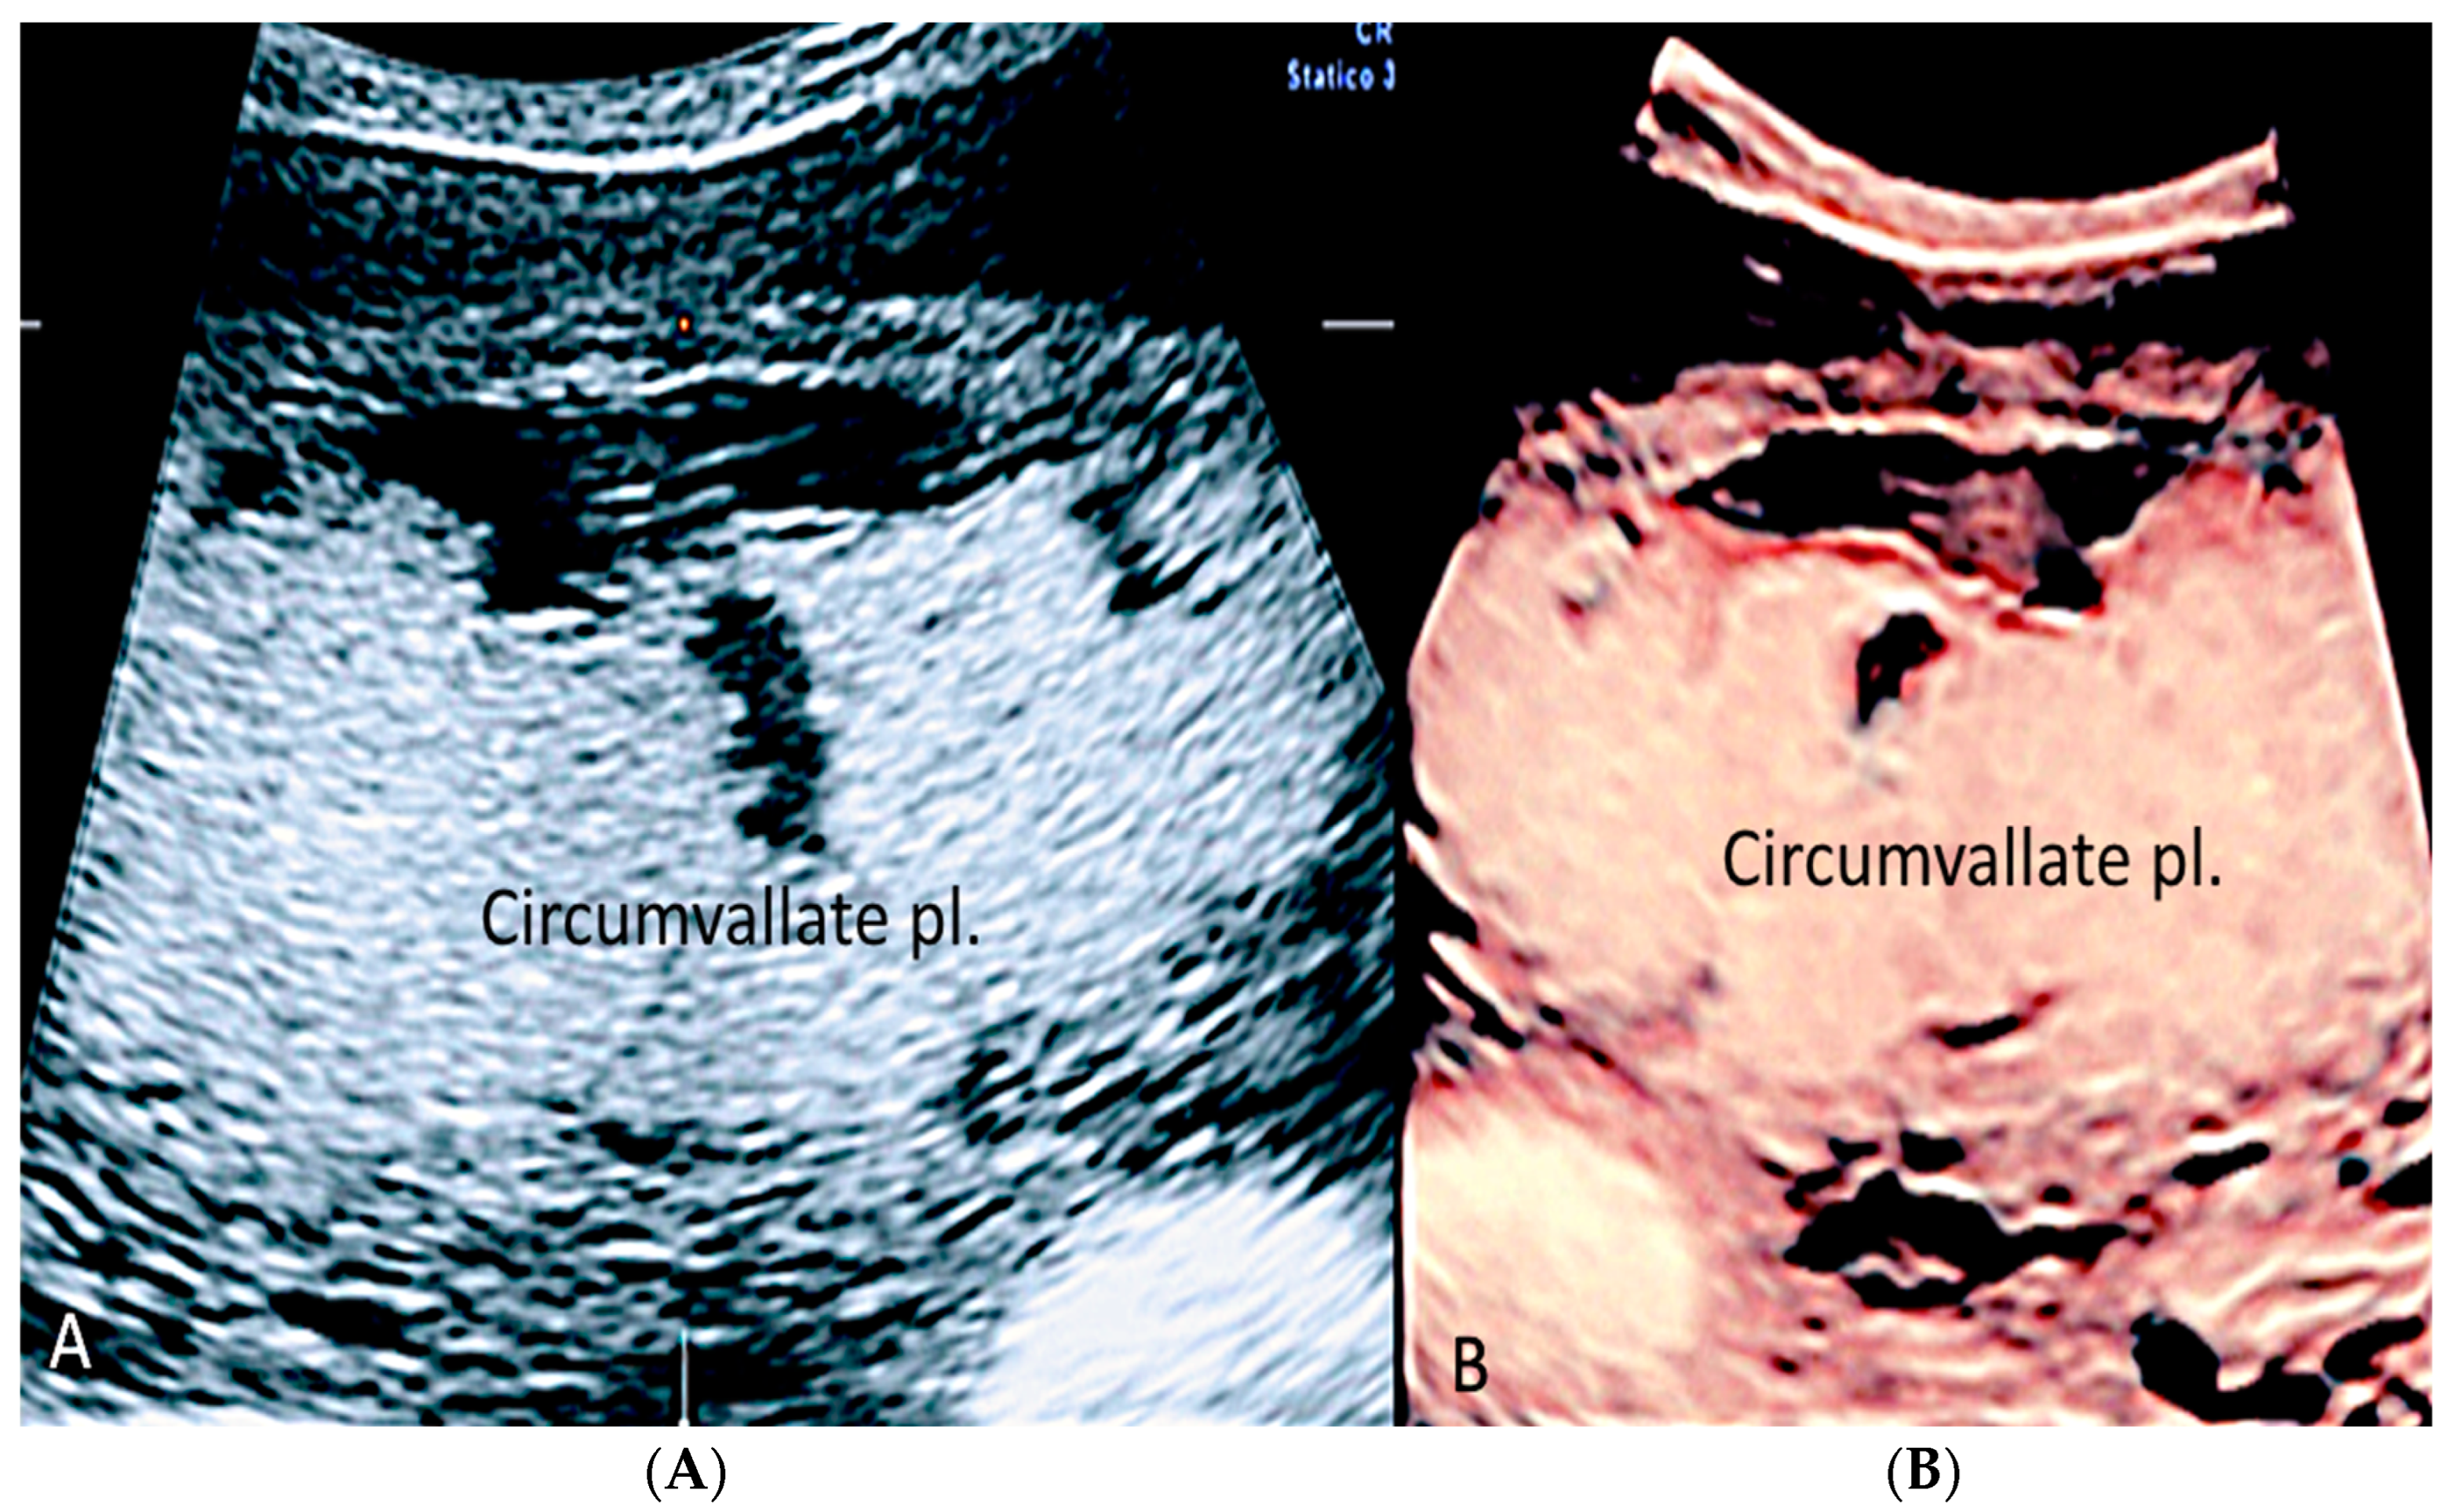

Circumvallate placenta is an abnormality in the area between the placental surfaces, in which the chorionic plate is smaller than the basal plate with protruding peripheral placental tissue [1,32,33]. It is associated with a higher risk of preterm delivery, vaginal bleeding during pregnancy, subchorionic hematoma, preterm premature rupture of membranes, placental insufficiency and placental abruption, especially when maternal serum alpha-fetoprotein is elevated (1.4 MoM) (multiple of the median) and when UtA-PI (uterine artery-pulsatility index) of 1.2 [27,32,33,34]. A sonographic diagnosis can be made during the 18–21 ultrasound week scan, when the average placental thickness is 2.74 ± 0.53 cm [33]. A raised edge of the placenta appearing as an echodense ridge and a circular depression with thick peripheral ring on the chorionic plate has been proposed by Arlicot et al. [35] as the “tire sign” and may be a useful clinical marker of circumvallate placenta when using 3D ultrasound [1,27,36]. (Figure 8, Figure 9 and Figure 10).

Figure 10.

(A,B) Fetal MRI (coronal T1 and T2) in a case of circumvallate placenta at 28 week’s gestation (white arrows).